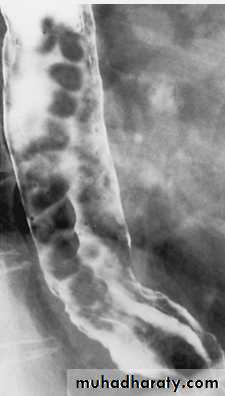

Barium enema: bowel preparation is important to get rid of the fecal material, barium is run into the colon under gravity, air is then blown in, to push the barium around the colon to give the double contrast effect. Barium enema is helpful in extensive diverticular disease being prepared for resection, colonic carcinoma, stricture, filling defect and ulceration.

Ulceration: recognized as small projections from the lumen into the wall of the bowel in a fuzzy or shaggy appearance. Caused mainly by ulcerative colitis & crohn's disease

Ulcerative colitis

Always involve the rectum, sometimes extends to involve the whole colonRadiological signs:

1.widespread shallow ulcer is the cardinal sign. Ulcers may be deep in severe cases2. widening of the presacral space due to peri-rectal edema

3. loss of the normal colonic haustra in the affected portions of the colon

4.narrowing and shorting of the colon giving the appearance of rigid tube

5.pseudopolyps ( swollen mucosa between ulcers) seen as filling defects

6.strictures are rare and likely to be due to carcinoma in longstanding disease

7.abnormal dilated ileum due to reflux through an incompetent ileocecal valve